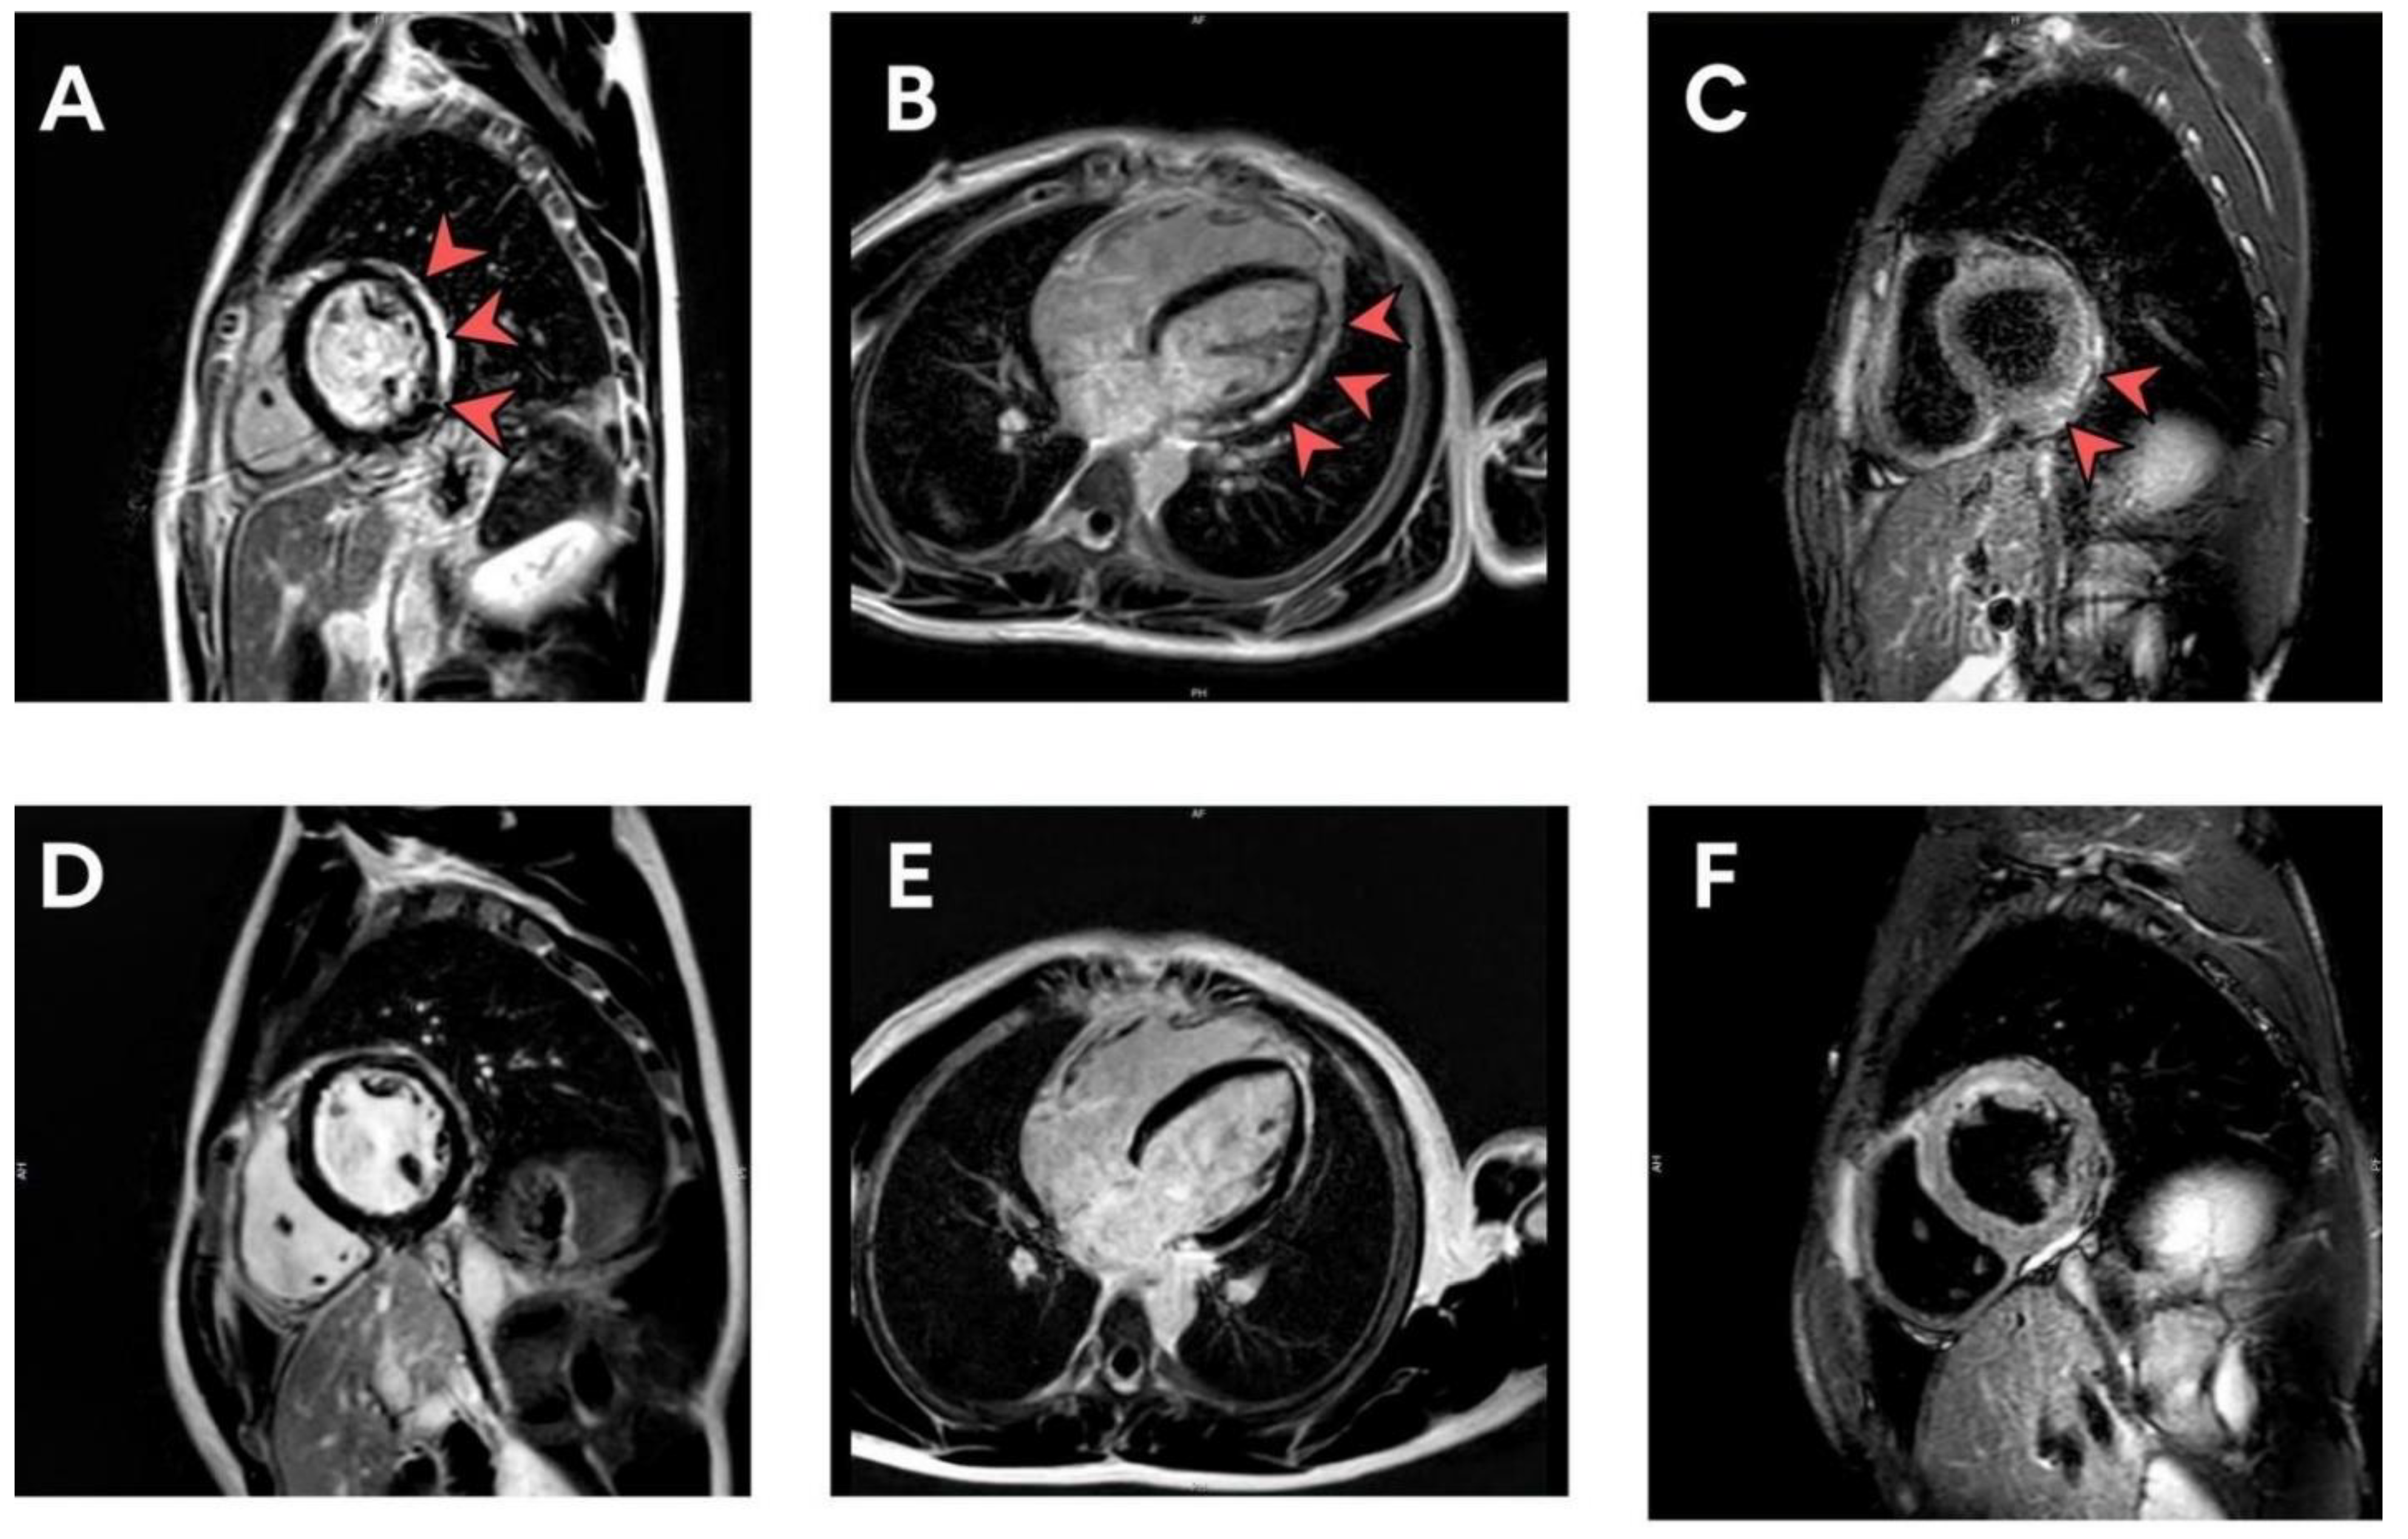

Cardiovascular adverse events observed during the study were tachycardia (7.64%), shortness of breath (6.64%), palpitation (4.32%), chest pain (4.32%), and hypertension (3.99%). Fifty-four patients had abnormal electrocardiograms (predominantly sinus tachycardia or sinus arrhythmia) after vaccination. All 54 of these patients had normal left ventricular ejection fraction. Three patients had minimal pericardial effusion. The cMRI revealed findings compatible with subacute myopericarditis (no evidence of myocardial edema with evidence of nonischemic delayed enhancement at lateral wall and pericardial enhancement at inferolateral wall) in one patient who was diagnosed with myopericarditis, as shown in Figure 2A–C. In addition, follow-up cMRI 5 months later showed no evidence of myocardial edema, myocardial delayed enhancement, or myocardial fibrosis. There is evidence of resolved myocarditis, as shown in Figure 2D–F. Incidental findings on echocardiography included a bicuspid aortic valve and a dilated coronary sinus from persistent left superior vena cava. Six patients had mitral valve prolapse, and six patients had hypertension (HTN). Three patients diagnosed with myopericarditis and pericarditis were treated with nonsteroidal anti-inflammatory drugs (NSAIDs) for 2 weeks with no residual symptoms and complete follow-up. The patients presenting with myopericarditis, subclinical myocarditis, and pericarditis are shown in Table 2.

Figure 2.

(A–F) cMRI illustrating LGE in a patient with subacute myopericarditis at the time of diagnosis (A–C) and 5 months post-diagnosis (D–F). cMRI, cardiac magnetic resonance imaging; LGE, late gadolinium enhancement.

In this study, one patient who was admitted to the ICU Department with negative PCR for COVID-19, was diagnosed with myopericarditis after mRNA COVID-19 vaccine, and showed abnormalities in cardiac enzymes (troponin-T, CK-MB), ECG, echocardiography, and cardiac MRI. As our patient remained clinically stable, endomyocardial biopsy was not indicated during hospitalization. He was treated with ibuprofen for 2 weeks without guideline-directed medical therapy for heart failure because his imaging showed normal LVEF. Treatment of vaccine-induced myocarditis includes corticosteroids, NSAIDs, colchicine, and, in severe cases, IVIG [32,33]. Corticosteroids have been proposed for the treatment of vaccine-induced myocarditis [33]. Nonpharmacological strategies to prevent cardiovascular side effects of COVID-19 vaccination include oral and systemic administration of ascorbic acid. An observational study has found that low serum ascorbic acid can increase cardiovascular disease in humans [34]. Ascorbic acid can prevent cardiotoxic events and can reduce the relative risk for cardiovascular events that could reduce inflammation related to cardiovascular events after COVID-19 vaccination [35]. All patients with subclinical myocarditis had elevated troponin-T without CK-MB elevation; troponin-T level was also highly sensitive for post-vaccination screening for myocarditis. Two patients diagnosed with pericarditis had normal troponin-T levels, but generally raised c-reactive protein (CRP) or erythrocyte sedimentation rate (ESR). All seven patients with elevated biomarker levels or positive lab assessments showed normal left ventricular ejection fraction (LVEF), and only three patients had minimal pericardial effusion. Conventional echocardiography may not be the ideal diagnostic tool in suspected vaccine-induced myocarditis because of its mild clinical symptoms; conventional echocardiography appeared normal in these patients. Speckle tracking echocardiography (STE) strain and strain-rate parameters are useful diagnostic measures with high sensitivity for the early detection of subclinical ventricular dysfunction [36], and cardiac MRI may be the best way to confirm a diagnosis of myocarditis in the majority of cases. In this study, the disease course was mild in all of our patients with cardiac symptoms; they were treated with ibuprofen for 2 weeks and cardiac enzymes returned to normal after 1–2 weeks of outpatient treatment. Myocarditis may have more severe clinical manifestations requiring inotropic drug or mechanical support; however, one patient with myopericarditis in our study follow-up with cMRI at 5 months post-vaccination showed complete recovery and no scar. If an adolescent presents with myopericarditis after COVID-19 mRNA vaccination, a booster shot is contraindicated.